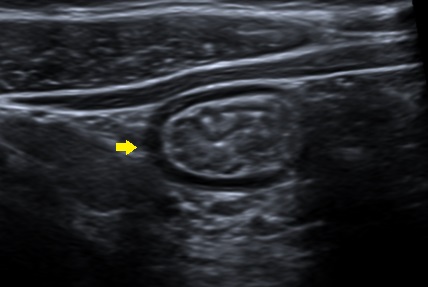

Niño de 13 años que ingresa por dolor abdominal en el hemiabdomen izquierdo y la fosa ilíaca derecha, intermitente, de dos semanas de evolución, asociando 1-2 deposiciones al día de consistencia líquida, con sangre roja al limpiarse en una ocasión, y vómitos y febrícula en los últimos tres días. No tiene tratamiento farmacológico habitual. Asma de esfuerzo. La familia describe otros tres episodios similares al descrito en los últimos 12 meses, de unas 3-4 semanas de duración, y por los que estaba siendo estudiado en otro centro. Durante el ingreso se realizan las siguientes pruebas complementarias: coprocultivo, parásitos en heces y toxina de C. difficile (negativos); calprotectina fecal: 90 mg/kg; bioquímica sanguínea (normal); hemograma (eosinofilia de 10 900/mm 3); ecografía abdominal: engrosamiento de asas en fosa iliaca derecha e hipocondrio izquierdo ( Fig. 1); gastroscopia sin hallazgos y colonoscopia con datos macroscópicos de ileítis terminal. Se recibe estudio anatomopatológico, que muestra una eosinofilia tisular intensa, más marcada en el íleon terminal y el ciego. En la ecografía de control a los tres meses persiste cierto engrosamiento de asas, con ligera mejoría respecto a imagen previa y analítica de control con normalización de la cifra de eosinófilos. El noveno mes de seguimiento el paciente presenta un episodio de febrícula, dolor abdominal intenso en fosa ilíaca derecha y vómitos, que es manejado con prednisona oral a 1 mg/kg. Evolución clínica posterior favorable.